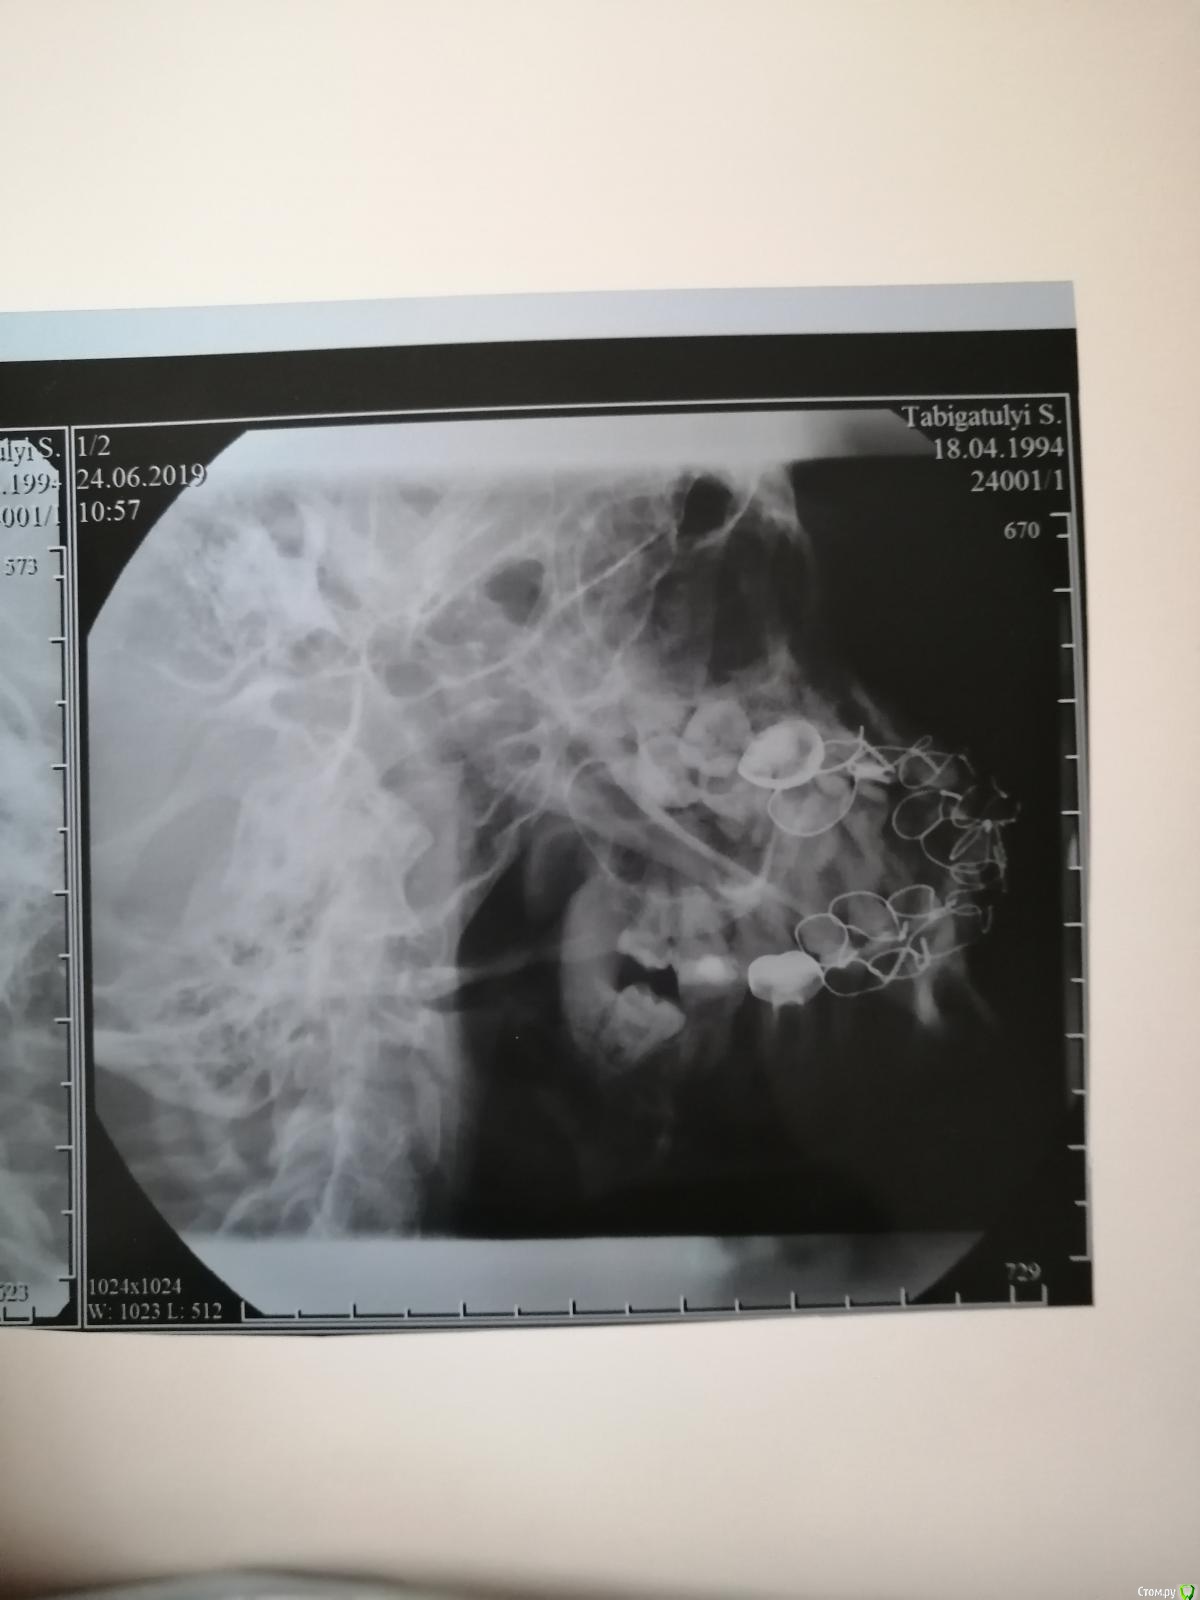

Blazingstar Опубликовано 16 июля, 2019 Поделиться Опубликовано 16 июля, 2019 (изменено) Перелом венечного отростка со смещением отломков. Сломал челюсть 16 июня прошлого месяца, обратился с болями в местную больницу к стоматологу, прописали антибиотики и сказали, что всё срастётся главное нё кушай твёрдое, потом 21 июня по собственной инициативе обратился в Члх, там сразу поставили шины если её не ставить сказали потом рот будет вонять всегда, там лежал 10 дней, в стационаре кололи антибиотики и вот сняли сегодня шины в местной больнице стоматолог посоветовал не есть три четыре дня твёрдую пищу. Во время лечения резинки не меняли ни разу когда лежал в стационаре и после в местной больнице, советовали только ромашкой полоскать. Пожалуйста посмотрите снимок срастётся ли всё нормально операцию не делали. Завтра на работу еду на вахту 15 дней. После снимок не делали. В стационаре сделали снимок зубов только спустя три дня, место перелома не снимали. Где череп это снимок до шинирования, остальные снимки после шинирования спустя три дня сделано(там не видно место перелома) . Изменено 16 июля, 2019 пользователем Blazingstar Ссылка на комментарий